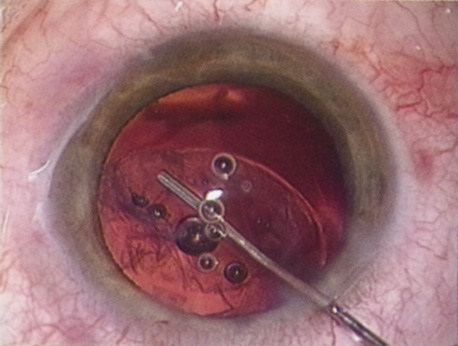

further tests guide the ophthalmologist in planning the surgery. SPECIAL MEASUREMENTS OF VISION Preoperative measurement of vision is meant to determine the patient's current state of visual function. Snellen acuity is routinely tested on all patients as part of their preoperative evaluation. This usually is performed by having the patient read a standardized chart in a darkened room. Although the Snellen acuity scale is the most ubiquitous measure of vision, it measures only one tiny aspect of visual function. Many patients may be profoundly functionally impaired by their degree of visual disability, yet may test surprisingly well measuring Snellen acuity in a darkened room. In these cases, it is incumbent on the ophthalmologist to seek to better understand and document the patient's problems by performing additional testing. Many patients are most bothered by cataract-induced glare. For these patients, acuity testing under glare situations is indicated. There are several methods to assess visual acuity reduction by glare. The choice of method is often best dictated by the patient's history. If a patient complains of glare problems in the supermarket, or other uniformly illuminated environment, the brightness acuity test can be performed (Mentor Ophthalmics). For this test, the specially illuminated handpiece is held in front of the tested eye using best spectacle correction (Fig. 1). The Snellen acuity is rechecked and can be recorded on each of three light settings. Patients who complain of glare from point sources of light, such as oncoming headlights or bright sunshine, may be best evaluated by a different form of glare testing. To simulate the environment of the patients' symptoms, Snellen acuity is measured while directing a point source of light obliquely toward the eye outside their best spectacle correction or outside of a phoropter dialed in with their best manifest refraction (Fig. 2). Still other patients' problems may center on difficulty with reading, seeing street signs, or distinguishing fine patterns. In these individuals, the complaints are related more to contrast; therefore, contrast testing is most appropriate. There are a number of ways to assess the effect of contrast on vision. Regan's sine wave gradients have been used frequently for research purposes and are available in some settings. Various commercial devices are now available to measure visual acuity in different contrast settings and each has its relative merits and detractions. The authors have found the Baylor Visual Acuity Tester (BVAT) monitor (Mentor Ophthalmics) testing of contrast to correlate well with patients' complaints and its simplicity is appealing to both patients and technical staff. In rare instances, patients' complaints may be primarily related to distinguishing colors. Although patients frequently remark about their dramatic improvement in color perception after cataract surgery, there are no convenient methods to document diminished color perception preoperatively. This underscores the importance of correlating patients' complaints with the biomicroscopic examination and the degree of nuclear color change. PROGNOSTIC TESTS Physicians often order special tests to help determine a patient's visual potential. Some of these tests are acuity specific. These can be particularly helpful in guiding patients who may have comorbid ocular conditions. Some devices have been designed to project a Snellen chart through the clearest area of the cataractous lens to assess retinal acuity potential such as the potential acuity meter. Studies also have shown a good predictive value by checking vision with a brightly illuminated near card.53 Of course, this can be performed with no additional office equipment. Various other commercial devices, including interferometry and various different pinhole and illumination device combinations, are available. These approaches are not possible for patients with mature cataracts. Some more general, nonspecific prognostic tests can be performed. If a patient is able to identify the colors of projected lights, this usually indicates that some cone-mediated macular function is present. Blue field endoscopy also may indicate some macular function. This test is performed by projecting a blue light into the eye. The patient may report seeing small round specks moving around in the vision. These specks correspond to white blood cells passing through the perifoveal capillaries. The Purkinje phenomenon is tested easily by rapidly wiggling a transilluminator directed toward the globe through the lower lid in a darkened room. If the patient reports a pattern of crooked lines or branches, then he or she is seeing the shadows cast by the retinal blood vessels, indicating that the posterior pole is attached and functioning to at least some degree. Although positive results from the test are encouraging, some patients may still have limited vision after surgery; similarly, some rare patients may test negatively on all these tests and still recover good vision. Diagnostic Studies Several diagnostic studies provide information that supplements the historical and clinical data obtained by the surgeon. This information enables proper preoperative patient consultation and surgical planning. This section outlines many preoperative tests used for cataract patients. A-SCAN BIOMETRY. Accurate axial length measurement is critical to determine the correct power of the implant lens for the desired refractive result. A-scan biometry is imperative in any patient undergoing cataract surgery. Both contact (applanation) and immersion varieties of A-scan ultrasound units are commercially available. With applanation biometry, a hand-held or slit-lamp mounted probe is gently touched to the corneal surface along the visual axis. Contact A-scans are user dependent and sometimes the authors adjust the surgeon-specific IOL A-constant depending on which ultrasonographer has performed the scan. Nonetheless, outstanding refractive outcomes have been achieved, and the authors have been satisfied with the contact applanation technique. With an immersion probe, a water bath around the eye acts as the medium to conduct sound waves. Although there is no direct contact of the probe with the globe, the water and water bath must, of course, remain in contact with the ocular surface and periorbita. Immersion scans may reduce interobserver variations but are less comfortable and less convenient for patients. A-scan biometry is particularly challenging in eyes containing an oil fill. In this instance laser biometry is still able to achieve excellent measures. LASER PARTIAL COHERENCE OPTICAL BIOMETRY. Although ultrasound requires continuous contact with media that conduct sound waves, laser light passes easily through any clear media, including air, making this a truly noncontact or “no touch” test. Furthermore, the speed of light is not appreciably different in the clear media of the eye and thus excellent, reliable measures can be achieved in eyes containing intraocular lenses, regardless of type and eyes with oil fills within the vitreous cavity. Although some calculation adjustments can be made depending on the pseudophakic status, the differences among implant material are not appreciable different from a practical clinical perspective. Currently, the only commercially available laser biometry device is the IOLMaster (Zeiss). The measurements obtained by the IOLMaster device are extremely reliable, reproducible, and seem to be relatively technician- and observer-independent.54,55This device also can measure keratometry, optical anterior chamber depth measurements, and “white-to-white” measurements in an automated fashion. Because it relies on the passage of laser light through the ocular media, this instrument is unable to obtain measurements in cases where the media prevent laser light passage; for example, white cataracts, axial posterior subcapsular cataracts, or corneal scarring. B-SCAN ULTRASOUND. A mature cataract precludes visualization of the fundus. A B-scan ultrasonographic examination provides a real-time, two-dimensional (2D), cross-sectional image of the globe along the marked axis of the probe (Fig. 3). Cataracts are more common in patients with chronic retinal detachment, prior trauma, or intraocular tumors; therefore, a B-scan study is helpful in excluding structural posterior segment pathology before surgery on a mature cataract. Although a negative result to B-scan evaluation is reassuring, the surgeon should remember that it does not predict postoperative visual outcome. The B-scan can be thought of as a picture of Cincinnati from an airplane; the office buildings may all be standing, but you cannot tell whether the people in them are working.